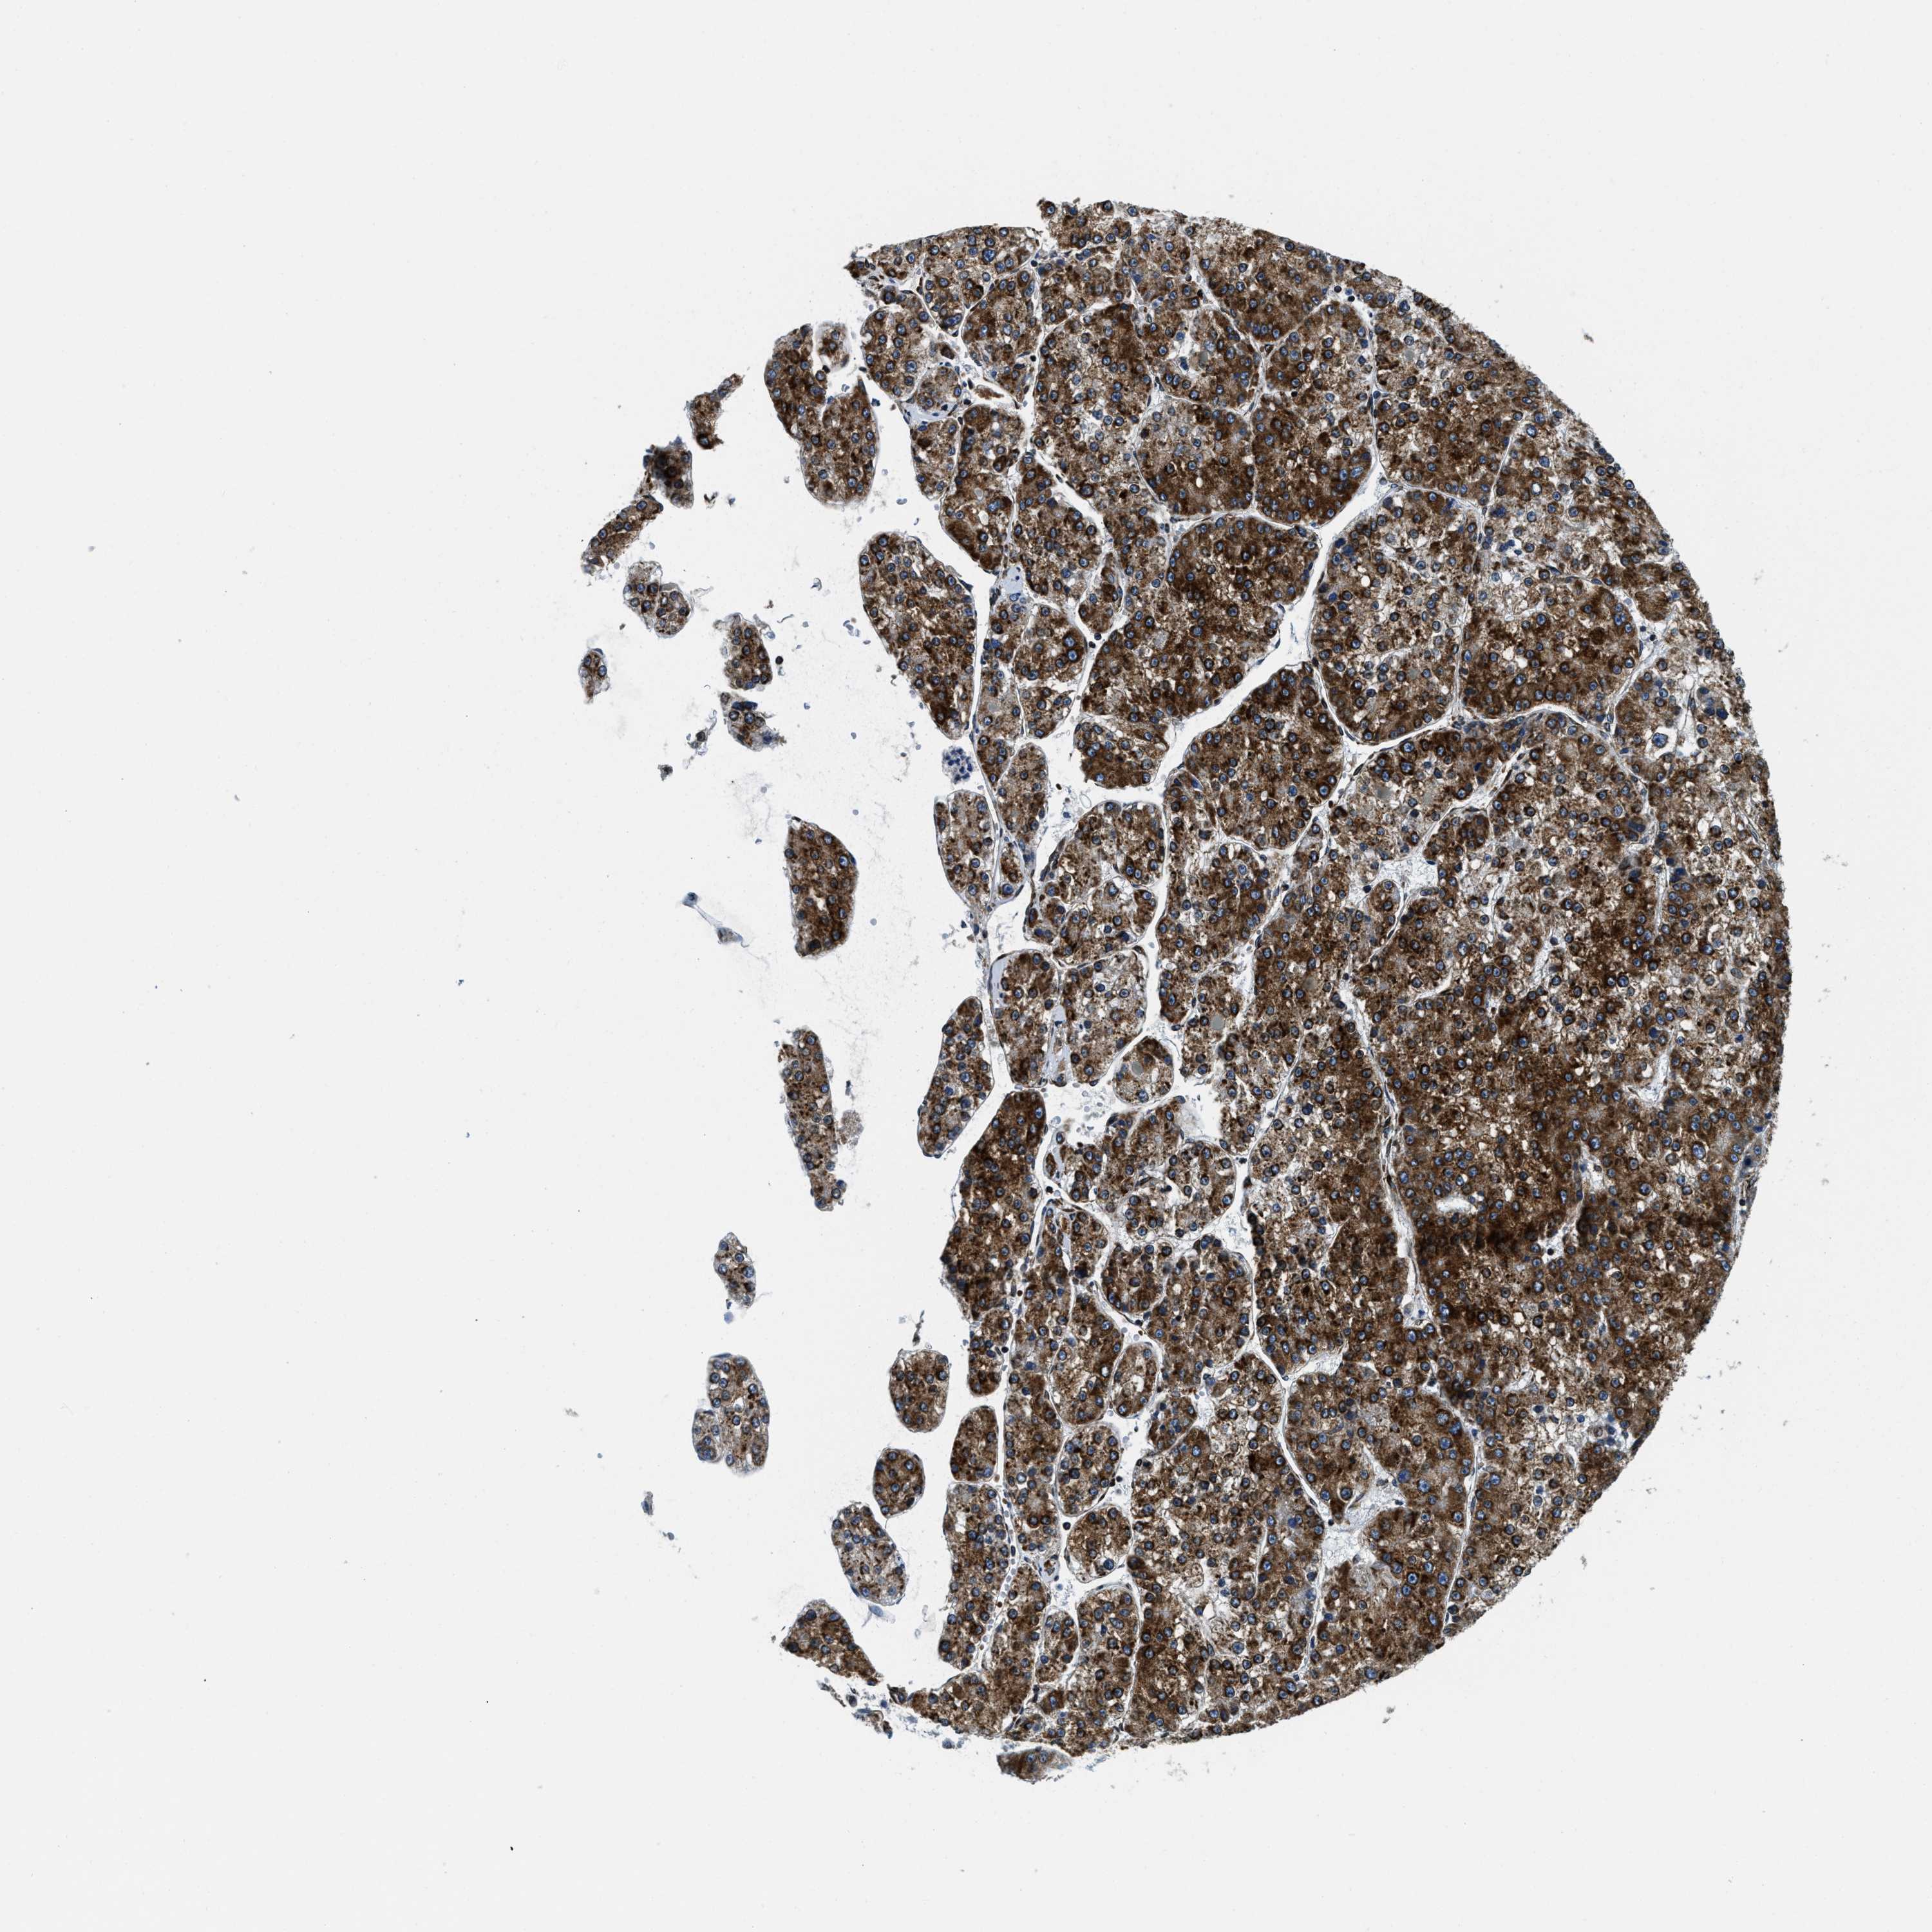

LIVER CANCER - Protein expressioni

A mouse-over function shows sample information and annotation data. Click on an image to view it in a full screen mode. Samples can be filtered based on level of antibody staining by selecting one or several of the following categories: high, medium, low and not detected. The assay and annotation is described here.

Note that samples used for immunohistochemistry by the Human Protein Atlas do not correspond to samples in the TCGA dataset.

Antibody stainingi

Antibody staining in the annotated cell types in the current human tissue is reported as not detected, low, medium, or high, based on conventional immunohistochemistry profiling in selected tissues. This score is based on the combination of the staining intensity and fraction of stained cells.

Each image is clickable and will lead to virtual microscopy that enables deeper exploration of all samples and also displays staining intensity scores, fraction scores and subcellular localization as well as patient and tissue information for each sample.

Antibody HPA019698

Staining

High

Medium

Low

Not detected

Intensity

Strong

Moderate

Weak

Negative

Quantity

>75%

75%-25%

<25%

None

Location

Nuclear

Cytoplasmic/membranous

Cytoplasmic/membranous,nuclear

Cholangiocarcinoma

Carcinoma, Hepatocellular, NOS